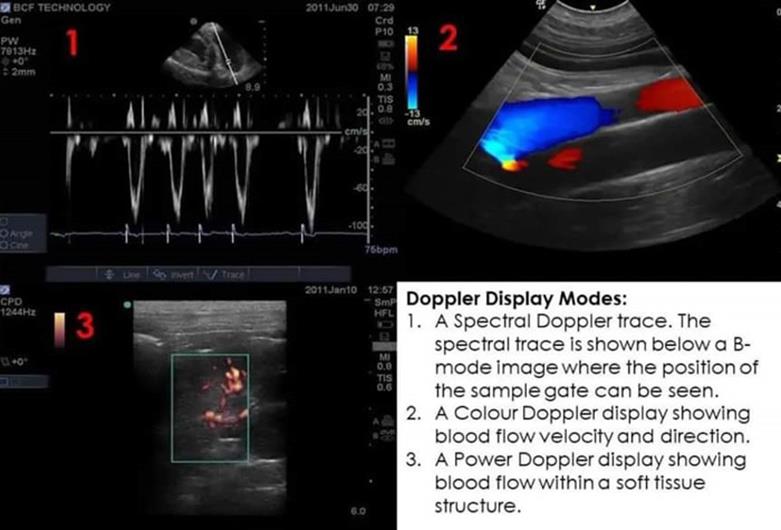

Hình ảnh kết quả siêu âm mạch máu của bệnh nhân

Kỹ thuật siêu âm mạch máu nhằm phát hiện các bệnh về mạch máu như: suy van tĩnh mạch chân, hẹp hoặc tắc nghẽn các động tĩnh mạch thận, cảnh, chi. Ngoài ra, khảo sát thăm khám giúp phát hiện các bệnh lý về mạch máu gan, thai sản, tầm soát đột quỵ…

Bên cạnh đó việc siêu âm mạch máu còn giúp bác sĩ tìm kiếm và nhận biết nơi hẹp hay tắc nghẽn hoàn toàn động, tĩnh mạch trong cơ thể, các bất thường như mãng xơ vữa hay cục máu đông từ đó có kế hoạch điều trị hiệu quả; Đánh giá cục máu đông ở hệ thống tĩnh mạch sâu; đánh giá những nơi phình hay giãn mạch máu; đánh giá hiệu quả điều trị…

Siêu âm mạch máu là kỹ thuật không gây đau, không xâm lấn. Thời gian thực hiện khá nhanh chóng. Trong khi đó, đo chức năng hô hấp là kỹ thuật khá đơn giản, dễ dàng thực hiện và không xâm lấn nên bệnh nhân sẽ không bị đau đớn và hầu như không gây khó chịu hay tai biến.